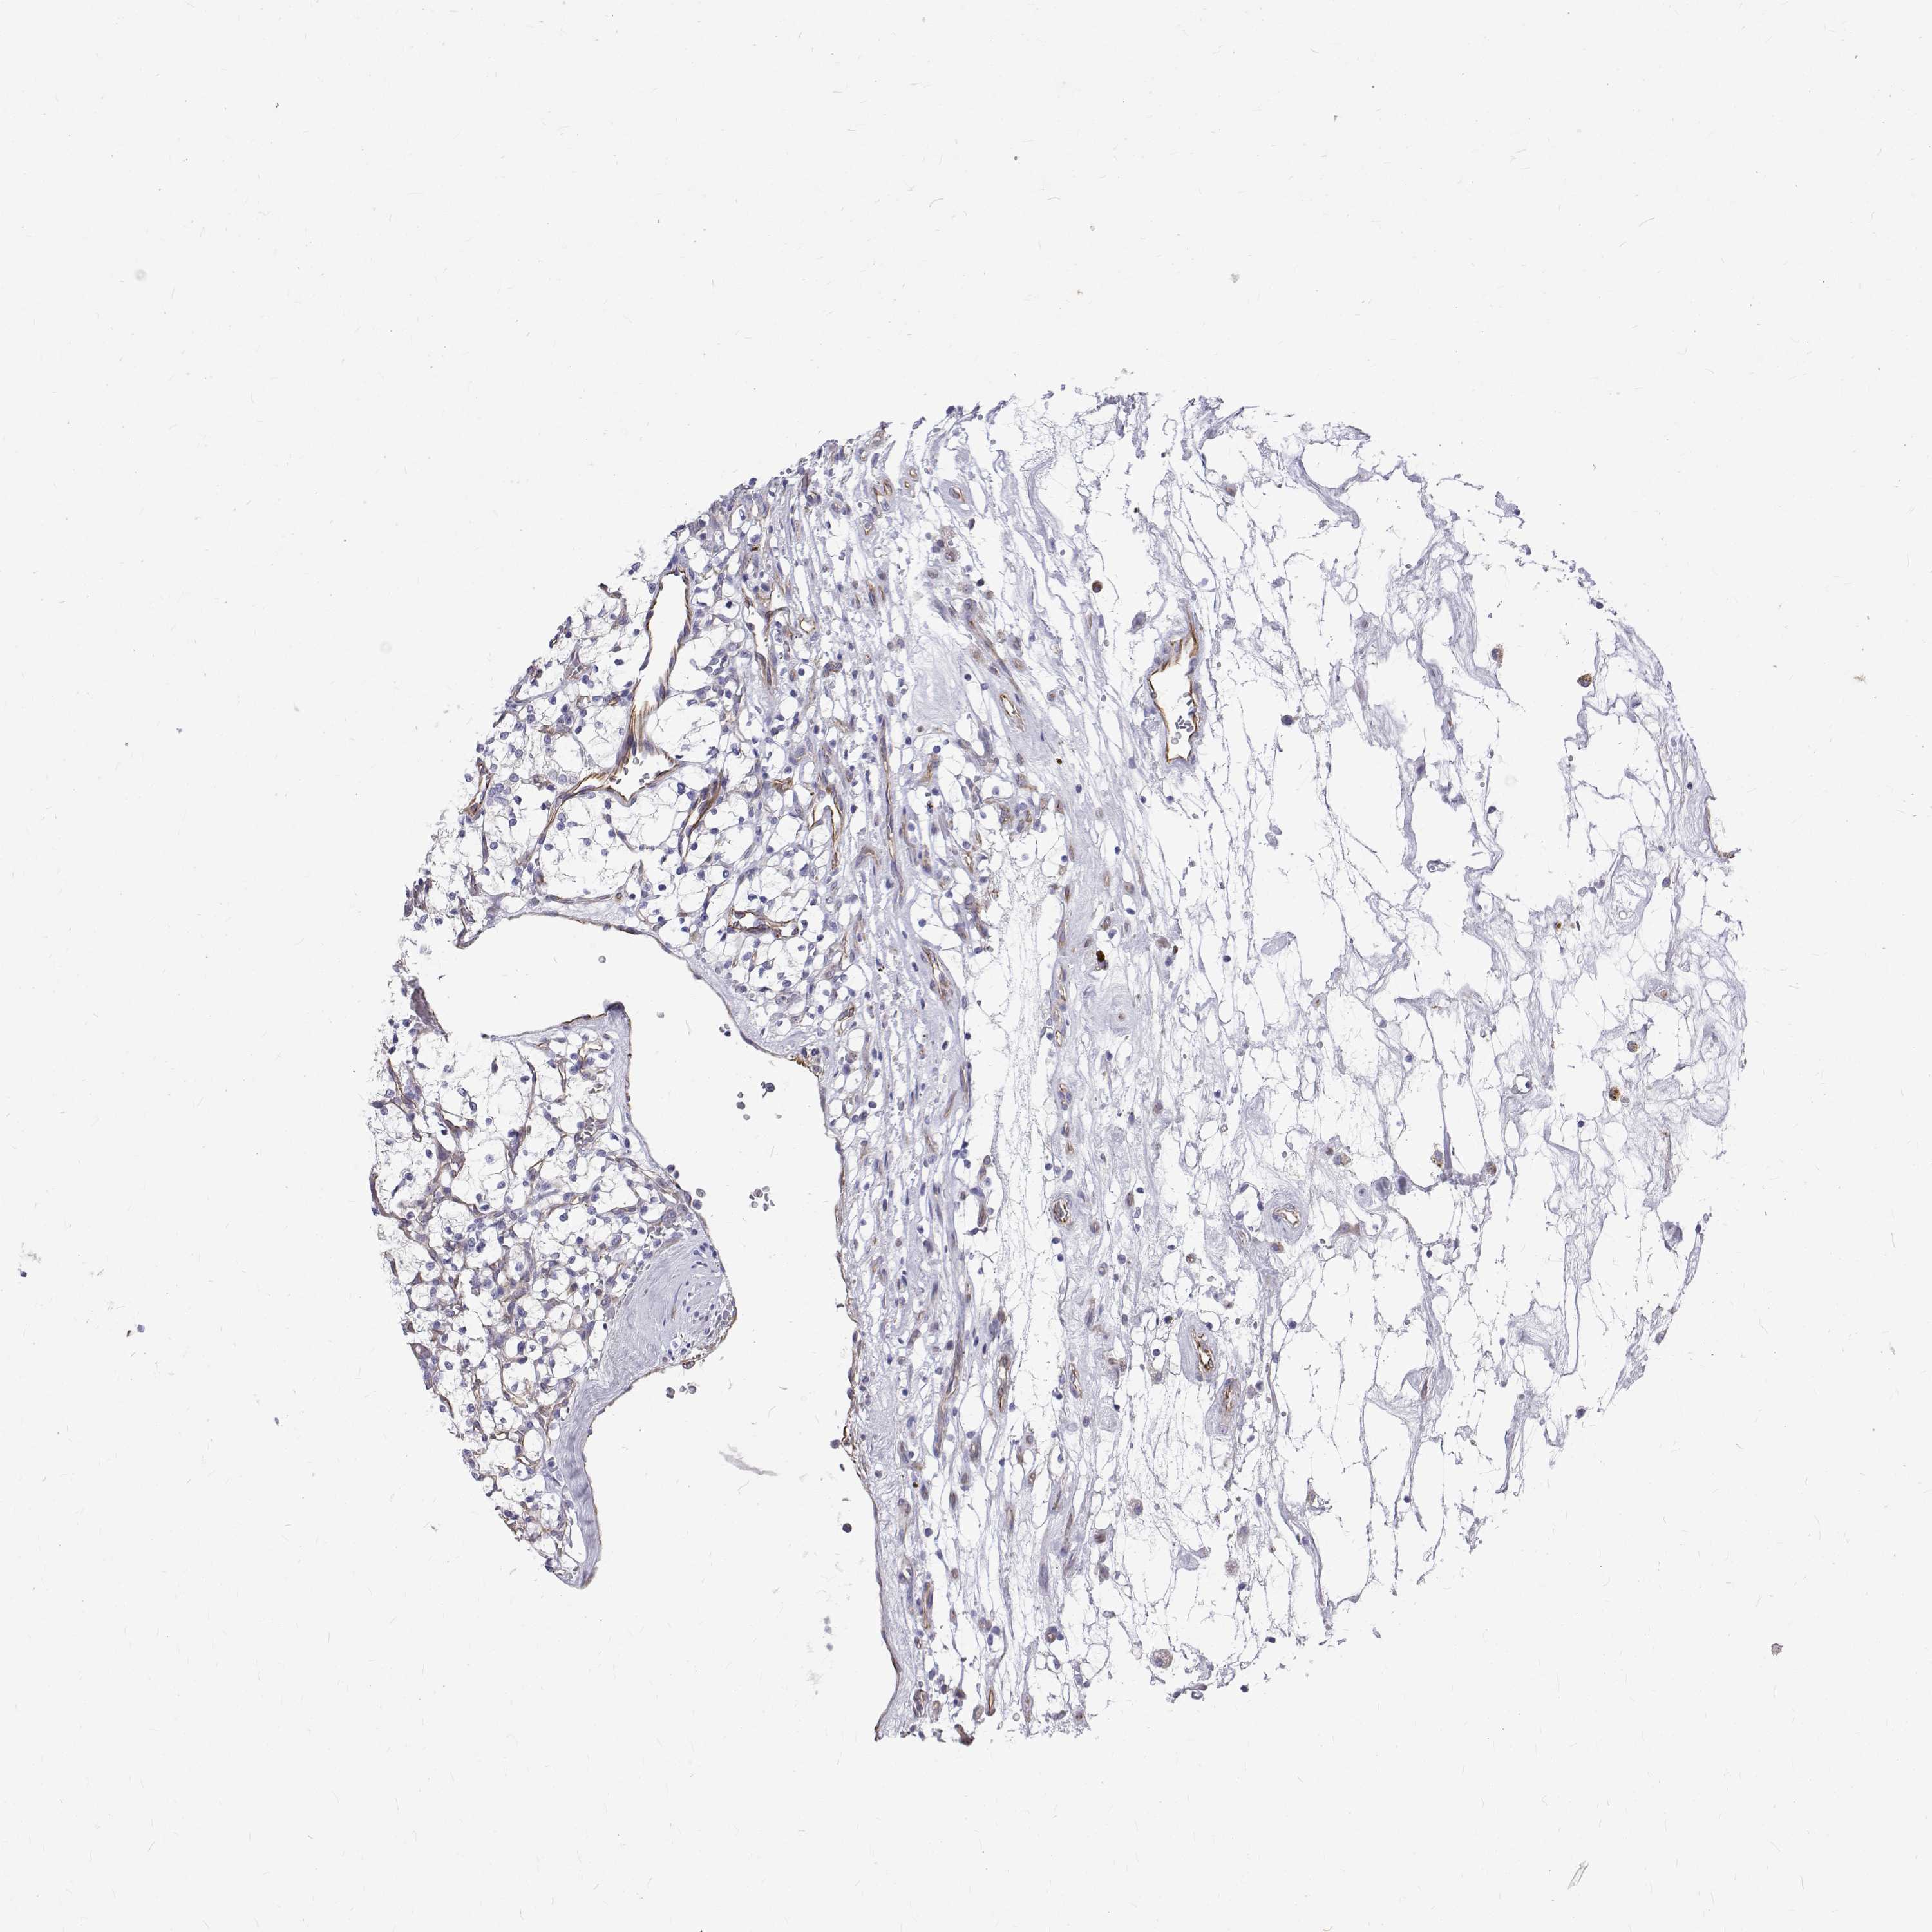

KIDNEY RENAL CLEAR CELL CARCINOMA (VALIDATION) - Interactive survival scatter ploti

The Survival Scatter plot shows the clinical status (i.e. dead or alive) for all individuals in the patient cohort, based on the same data that underlies the corresponding Kaplan-Meier plots. Patients that are alive at last time for follow-up are shown in blue and patients who have died during the study are shown in red.

The x-axis shows the expression levels (FPKM) of the investigated gene in the tumor tissue at the time of diagnosis. The y-axis shows the follow-up time after diagnosis (years). Both axes are complimented with kernel density curves demonstrating the data density over the axes. The top density plot shows the expression levels (FPKM) distribution among dead (red) and alive patients (blue). The right density plot shows the data density of the survived years of dead patients with high and low expression levels respectively, stratified using the cutoff indicated by the vertical dashed line through the Survival Scatter plot. This cutoff is automatically defined based on the FPKM cutoff that minimizes the p-score. The cutoff can be changed by dragging the vertical line or by entering a cutoff value in the square labeled "Current cut-off".

Under the Survival Scatter plot the p-score landscape (black curve; left axis) is shown together with dead median separation (red curve; right axis). Dead median separation is the difference in median mRNA expression between patients who have died with high and low expression, respectively. It is calculated as follows: median FPKM expression of dead patients with high expression - median FPKM expression of dead patients with low expression. This is intended to aid the user in visually exploring custom cutoffs and the associated p-scores and dead median separation.

Individual patient data is displayed and can be filtered by clicking on one or more of the category buttons on the top of the page. Categories describing expression level and patient information include: high, low, alive, dead, female, male and tumor stages. The scale of the x-axis can be toggled between linear and log-scale by clicking on the "x log" button. Mouse-over function shows TCGA ID, patient information and mRNA expression (FPKM) for each patient.

& Survival analysisi

Kaplan-Meier plots summarize results from analysis of correlation between mRNA expression level and patient survival. Patients were divided based on level of expression into one of the two groups "low" (under cut off) or "high" (over cut off). X-axis shows time for survival (years) and y-axis shows the probability of survival, where 1.0 corresponds to 100 percent.

Survival analysis data not available.

TCGA RNA samplesi

RNA-seq data is reported as average FPKM (number Fragments Per Kilobase of exon per Million reads), generated by the The Cancer Genome Atlas (TCGA) .

Normal distribution across the dataset is visualized with box plots, shown as median and 25th and 75th percentiles. Points are displayed as outliers if they are above or below 1.5 times the interquartile range. FPKM values of the individual samples are presented next to the box plot.

Average pTPM 0.0

Number of samples 100